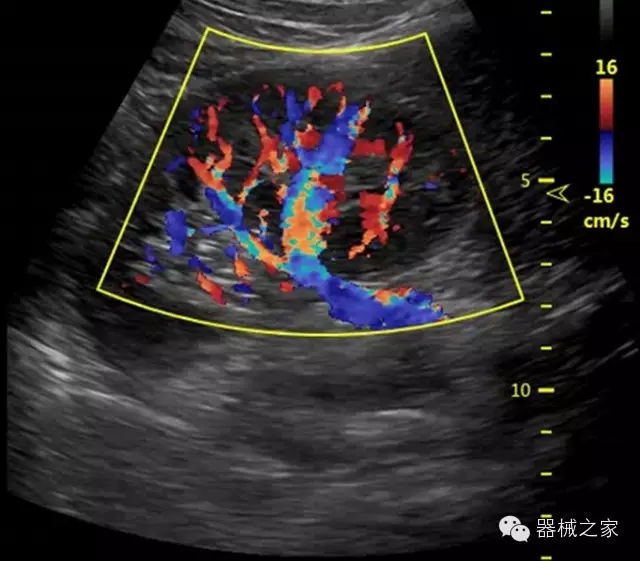

品牌:飛依諾(VINNO)

公司簡(jiǎn)介:

飛依諾科技(蘇州)有限公司2010年在蘇州工業(yè)園區(qū)成立,公司致力于成為世界一流醫(yī)療超聲品牌。核心創(chuàng)始團(tuán)隊(duì)囊括了來(lái)自于全球著名公司十多位資深研發(fā)和市場(chǎng)人才,均為業(yè)界精英。

官方網(wǎng)站:www.vinno.com

經(jīng)典產(chǎn)品:VINNO 6

臨床圖片賞析

產(chǎn)品特點(diǎn)

·獨(dú)有的RF平臺(tái)提高微小細(xì)節(jié)顯示、圖像對(duì)比度和邊界清晰度;

·特有的XCEN探頭,超寬的帶寬,表現(xiàn)更高分辨率和對(duì)比度;

·單晶純凈波探頭提供更佳的穿透力和彩色敏感度;

·完整的3D/4D臨床應(yīng)用,STIC, MCUT 和Auto NT等滿足產(chǎn)科所有應(yīng)用;

·更高的HQ羊膜腔鏡成像技術(shù)精細(xì)觀察每一個(gè)暗區(qū)細(xì)節(jié);

·智能的觸摸屏界面,能任意角度方位旋轉(zhuǎn)3D圖像,以及注釋快速標(biāo)記,提供直觀與便捷的操作,提高了工作效率;

介入室/手術(shù)室

·Needle Enhancement 穿刺增強(qiáng)技術(shù),清晰顯示穿刺針尖,定位目標(biāo)精確穿刺;

·智能的聲控功能,以及全屏顯示真正意義上解決醫(yī)生術(shù)中應(yīng)用;

Xcen探頭技術(shù)

·獨(dú)有的Xcen高頻18MHz探頭,使微小病灶的顯示成為現(xiàn)實(shí),為臨床提供了更廣泛的臨床應(yīng)用;

·Xcen超寬頻帶探頭技術(shù)比常規(guī)探頭頻寬提高了30%,具有更廣泛的臨床應(yīng)用,更高的頻率讓我們獲得了更好的細(xì)微分辨率和對(duì)比度的圖像;

肌骨理療

·智能感知組織特異性的VTissue技術(shù),結(jié)合特有高達(dá)22MHzXcen線陣探頭, 以及獨(dú)有敏感的RF射頻血流提供了優(yōu)異臨床圖像;

·智能的教學(xué)操作流程提供全面及專業(yè)的操作步驟指導(dǎo),便捷藍(lán)牙傳輸保障信息流暢;

便捷傳輸功能

·藍(lán)牙傳輸/ WIFI 郵件/ 移動(dòng)網(wǎng)絡(luò)/ DICOM;

·ICU/CCU;

·飛依諾特有心臟純凈波探頭提供更好的穿透力和彩色敏感度,以及結(jié)合TView梯形拓展改善困難病人深部組織成像;

·獨(dú)有RF敏感血流使得心臟血流完美呈現(xiàn);

CFDA注冊(cè)證編號(hào)

·國(guó)械注準(zhǔn)20152231021